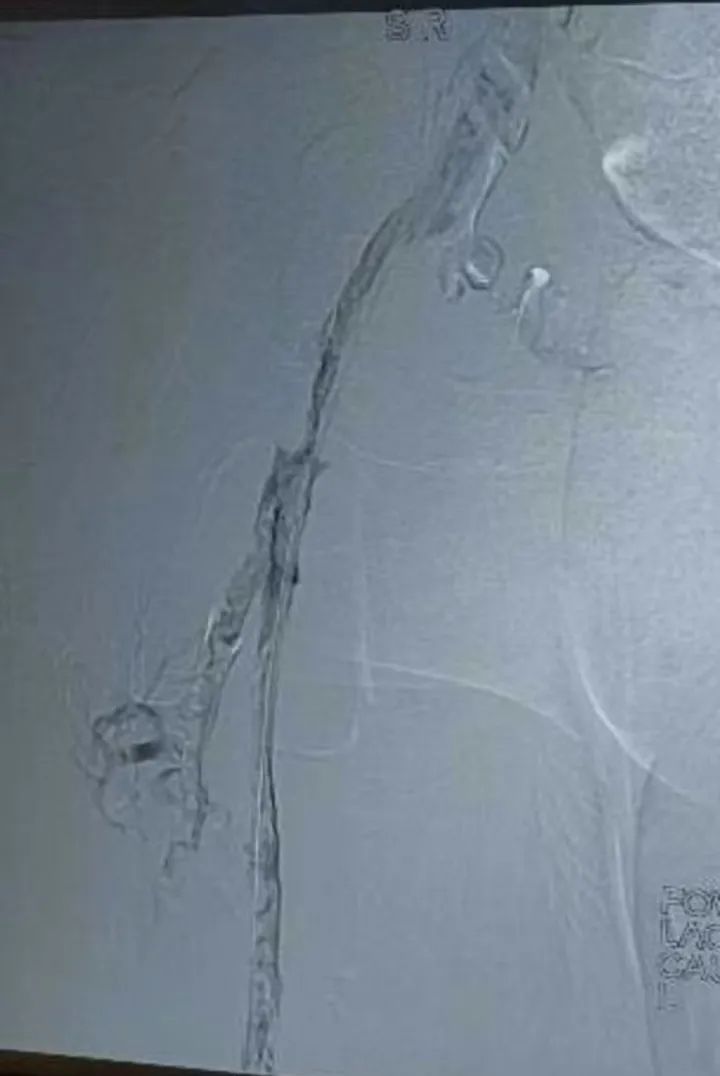

术中造影证实左下肢全肢型深静脉血栓形成

滤器置入

放置溶栓导管

导管直接接触溶栓(Catheter-Directed Thrombolysis, CDT),目前是各种指南推荐级别较高的一种DVT(深静脉血栓形成)的治疗手段,溶栓药物经过溶栓导管的侧孔直接进入血栓的内部,直接接触血凝块,溶栓效果良好。